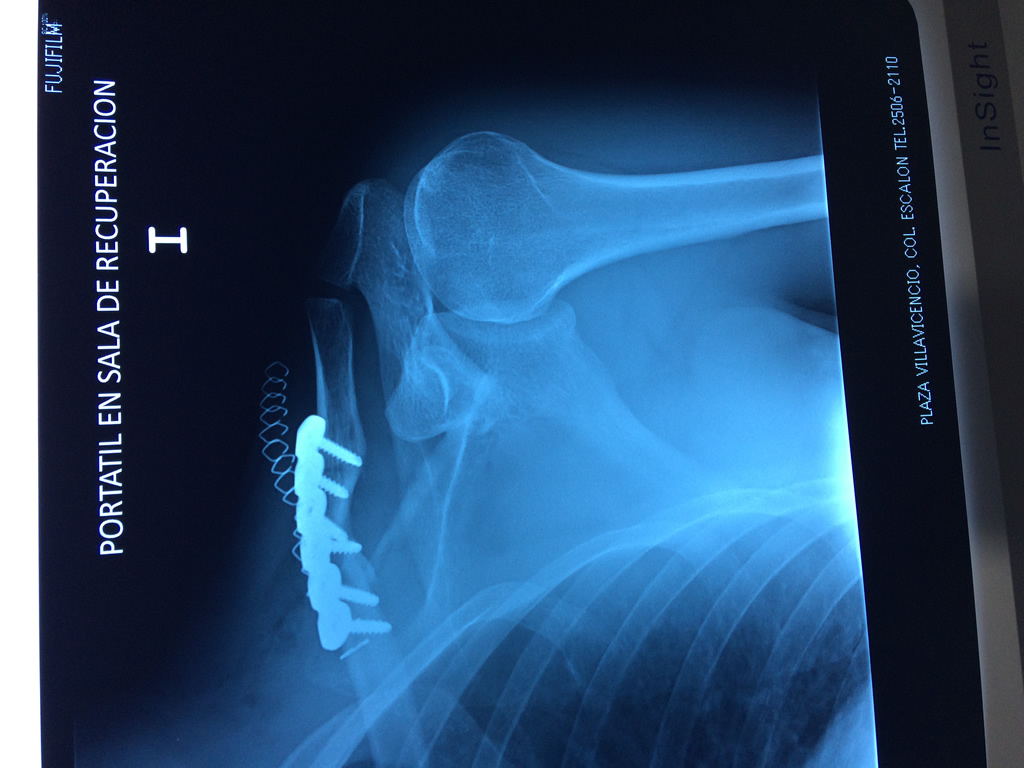

La clavícula es un hueso largo, con forma de "S" itálica, situado en la parte anterosuperior del tórax. Junto con la escápula forman la cintura escapular. Se puede palpar por toda su longitud y se extiende del esternón al acromion de la escápula, siguiendo una dirección oblicua lateral y posterior.